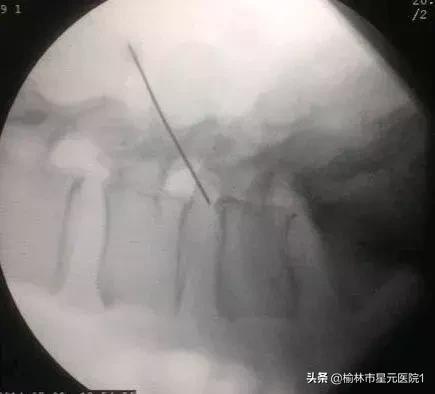

术前定位